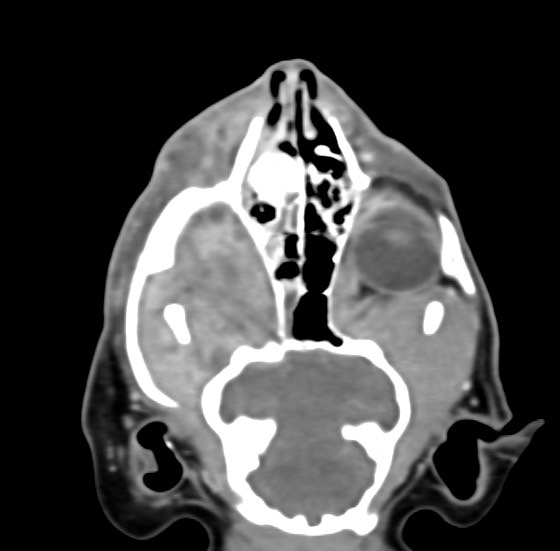

狗狗 鼻腔腫瘤 惡性上皮癌

鼻腔腫瘤的診斷需要仰賴電腦斷層掃瞄定位病灶處,同時使用鼻腔內視鏡探查、採樣才能確診,同時有這兩項設備的醫院並不多,所以臨床上並不是那麼容易確診。狗狗的慢性鼻炎維持3-4個月,越來越嚴重,他院轉診至築心,經由內視鏡+電腦斷層確認為鼻腔上皮癌,而且由於病程時間長,已經轉移至胸腔,代表壽命不長了,至少家人心中有個答案,有心理準備陪狗狗最後一段路。

狗狗 鼻腔腫瘤 淋巴癌

鼻腔腫瘤的診斷需要仰賴電腦斷層掃瞄定位病灶處,同時使用鼻腔內視鏡探查、採樣才能確診,同時有這兩項設備的醫院並不多,所以臨床事並不是那麼容易確診。狗狗如果有打噴嚏、鼻分泌物 鼻塞,對藥物治療反應不好, 就還是要做進一步檢查才會比較安心唷!